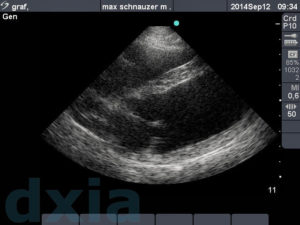

Imágenes obtenidas durante el estudio ecocardiográfico

Eje corto max

Eje corto derecho

No aplastamiento del septo IV. Contracción conservada. Base cardíaca. No dilatación de aurícula izquierda.